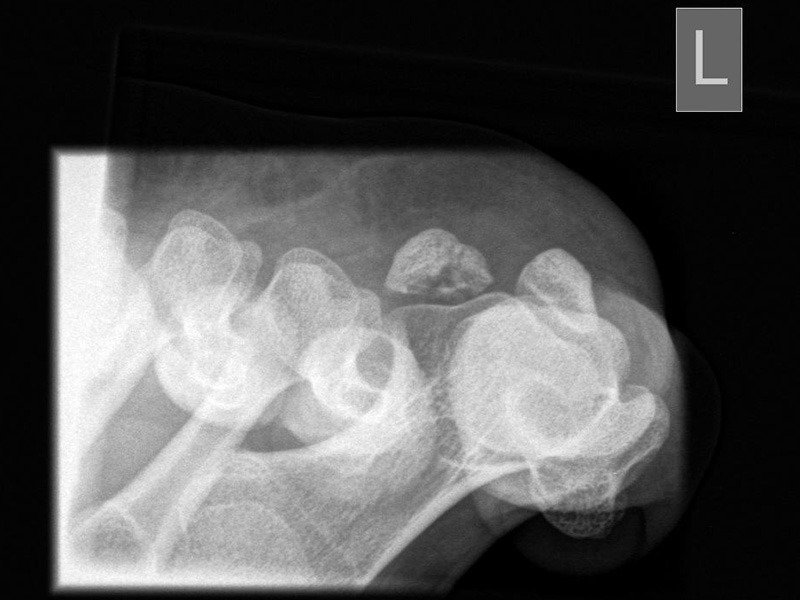

pa (posterior-anteriore) axiale Aufnahme der Sesambeine (Sprinteraufnahme)

Positionierung:

• Patient in Bauchlage, Knie durch Schaumstoffmatte unterstützt.

• Zehen in maximaler Dorsalextension.

• Zentralstrahl fokussiert auf das Großzehengrundgelenk.

• Röntgenröhre 0° vertikal.

• Filmposition horizontal.

Kennzeichen des Röntgenbildes:

• Tangentiale Abbildung des Sesambeingleitlagers.

• Abbildung des Vorfußreliefs.

• Pathologien der Gleitrinne sind gut erkennbar.

• Dislokation der Sesambeine aus der Gleitrinne sind gut erkennbar.

• Abbildung von Protrusionen einzelner Metatarsalia oder Sesambeine.

Besondere Anmerkungen zum Beispielbild:

• Sehr kräftig ausgebildetes mediales Sesambein bei einem Patienten mit chronischen Druckbeschwerden an dieser Stelle.

• Beide Sesambeine sind in der Gleitrinne zentriert.

Zur Vollansicht und zum Lesen der Bildbeschreibung bitte die Bilder anklicken.

ap (anterior - posteriore) axiale Aufnahme der Sesambeine

• Patient in Rückenlage, Ferse auf der Filmplatte liegend.

• Sprunggelenk in 15°-Spitzfußstellung.

• Maximale Dorsalextension der Zehen mit einer Schlaufe.

• Fragmentationsstadium bei Osteonekrose des lateralen Sesambeins.